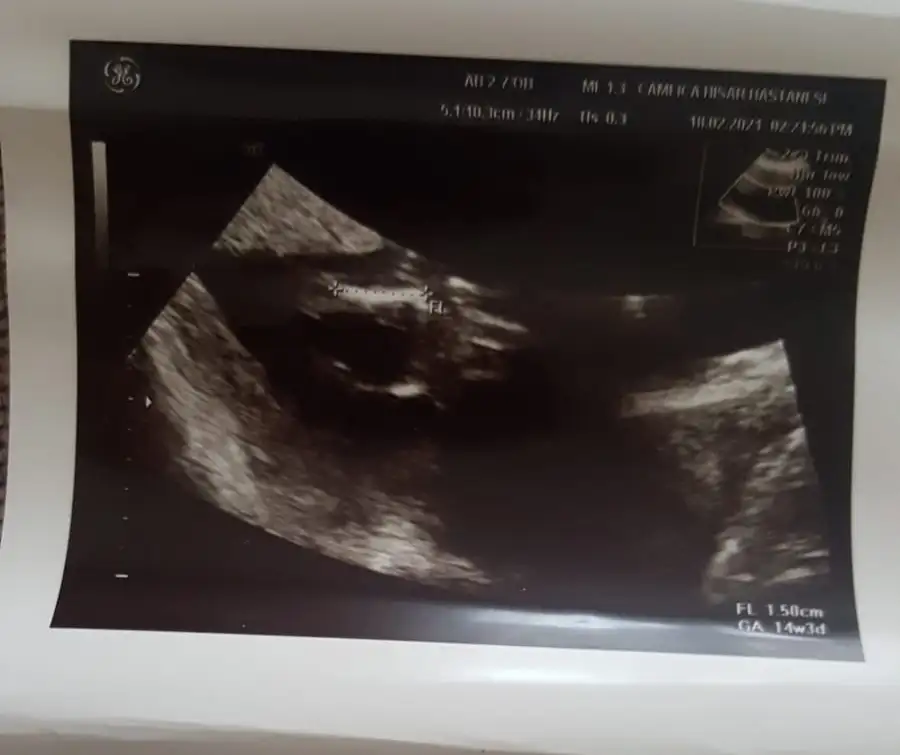

Kız sanki emin olamadımBana da tahminde bulunur musunuz 11 haftalık![]()

Net değil USG başka USG varsa paylaşın sanki kız gibi amin olamadım12+5 acaba tahminde bulunabilir misinizEki Görüntüle 2785401

12.hafta burdaKız sanki emin olamadım 12-13 hafta olursa paylaşın

12+2Kız sanki emin olamadım 12-13 hafta olursa paylaşın